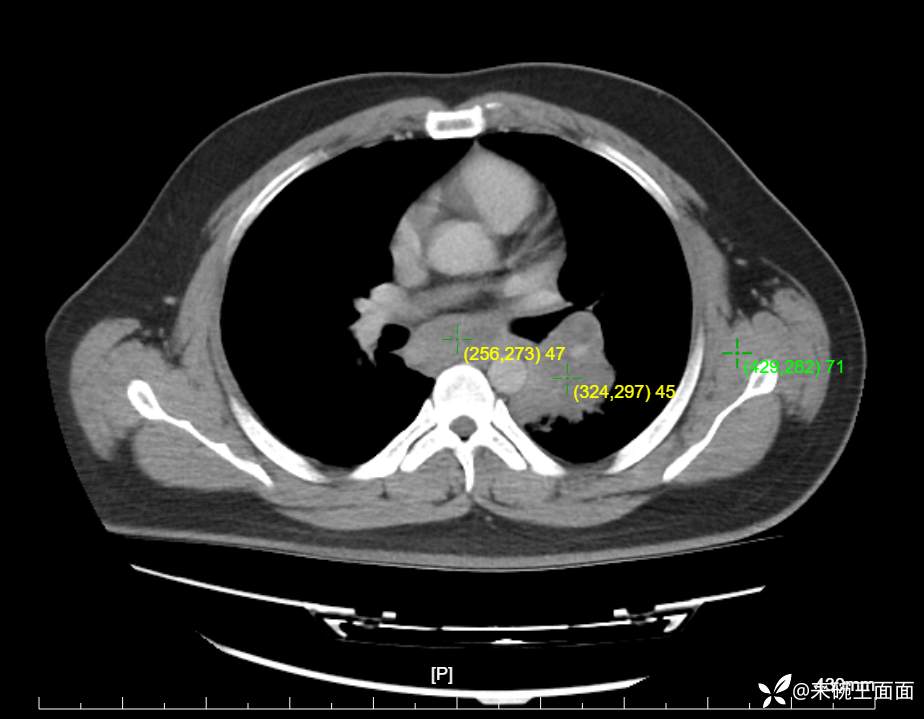

性别:男

年龄:27岁

主诉:胸闷胸痛数月余,休息后可自行缓解,无咯血症状。

个人史:数年吸烟史,具体不详。